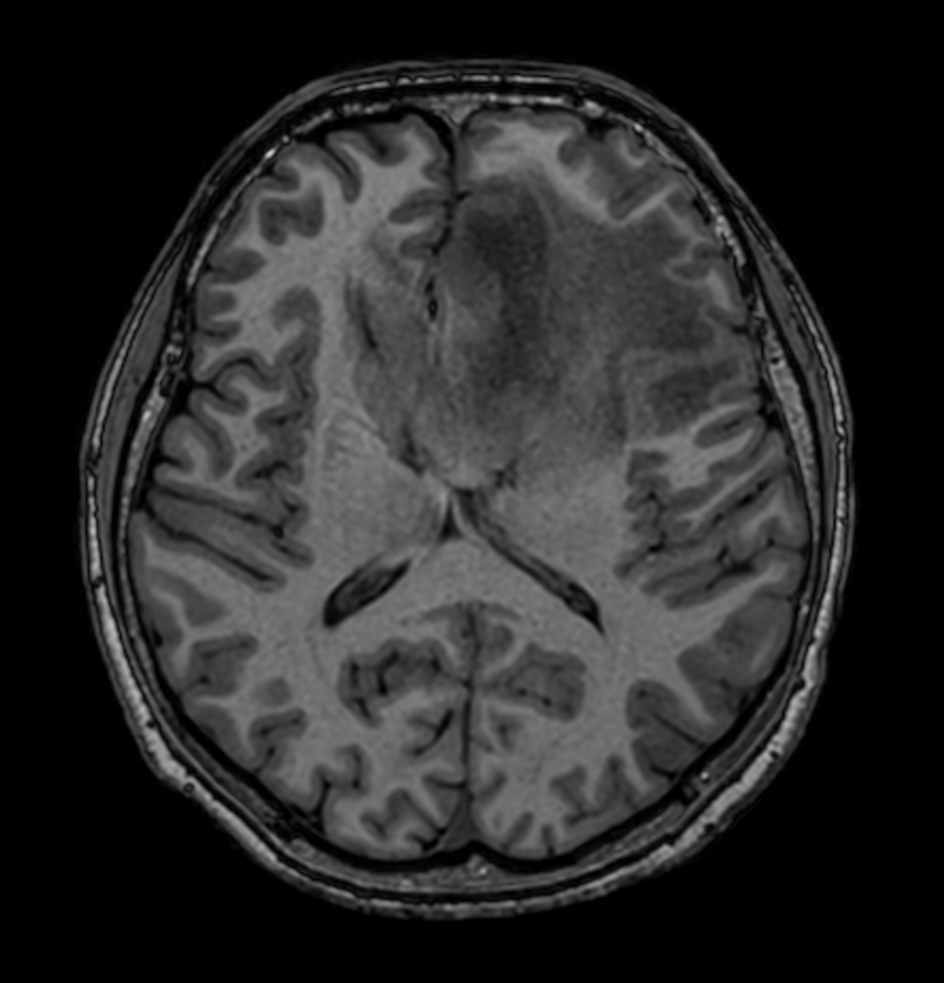

3D T1w TFE